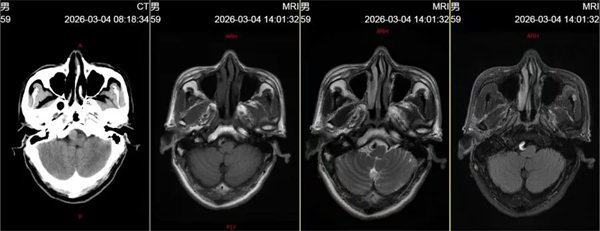

该患者平素身体健康,无基础疾病史,因发作性头晕症状入院检查。入院后,迅速为其完善头颅CT及MRI检查,初步发现双侧额顶叶及侧脑室体旁腔梗灶,且右侧椎动脉V4段存在瘤样扩张,高度怀疑颅内动脉瘤。为进一步明确病变细节,神经内一科团队及时为患者实施全脑血管造影术(DSA),最终确诊为右侧椎动脉V4段梭形动脉瘤,瘤体大小约13mm×20mm。